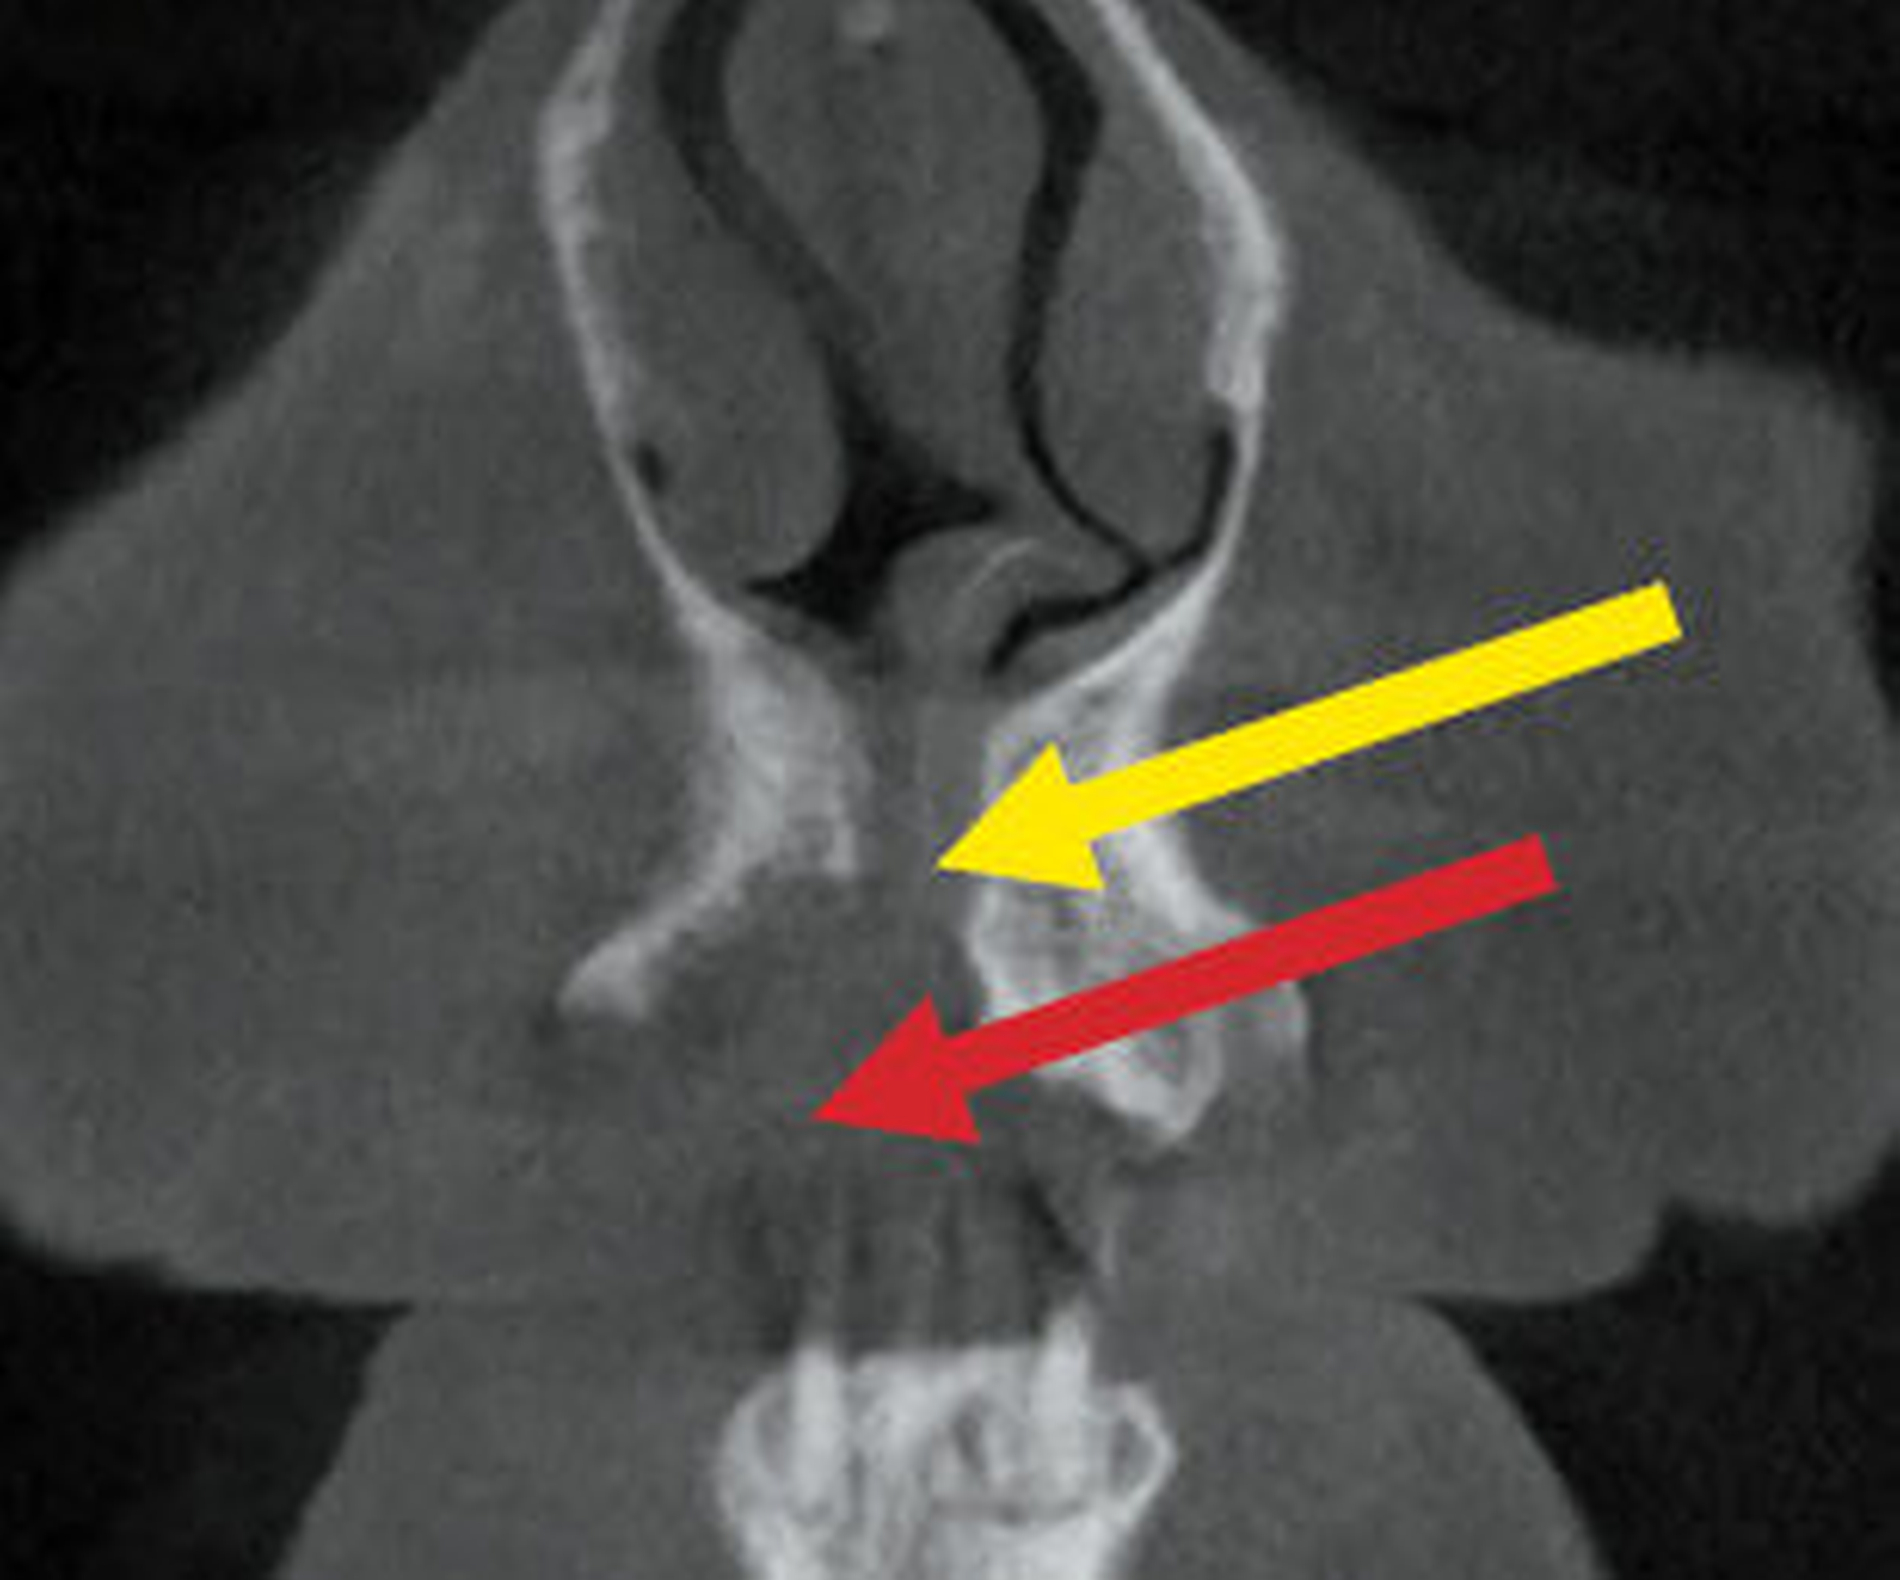

Im DVT sind in allen Raumebenen deutliche Knochendefekte zu erkennen, die zur Unterbrechung des Alveolarfortsatzes in der OK-Frontzahnregion führen. Zusätzlich grenzt sich ein breiter Canalis incisivus ab (Abbildungen 2 bis 4). Ein Rückschluss auf Pathologien im bezeichneten Bereich lässt sich aus den vorliegenden radiologischen Unterlagen nicht ziehen.

Für den vorliegenden Zweck war eine Untersuchung mit zwei Sequenzen notwendig: zum einen mit der sogenannten „Anatomie“-Sequenz (anatomy_3D_overview), zum anderen mit der „Inflammation-“ oder „Entzündungs-“Sequenz (inflammation_3D_overview). Während die Anatomie-Sequenz einen räumlichen Überblick ermöglicht, kann man mit der Inflammation-Sequenz Entzündungsprozesse identifizieren (Abbildungen 5 und 6) – die entsprechenden Lokalisationen erscheinen in der Aufnahme hell (hyperintens).

Die Anatomie-Sequenz wird regelmäßig bei nahezu allen Untersuchungen verwendet, weil sie hochaufgelöst die räumliche Lokalisierung anatomischer Strukturen erlaubt. Sie gibt in Analogie zur sogenannten PD-Sequenz die Dichte an Wasserstoffprotonen im Gewebe wieder. Wasser- und fettreiche Strukturen (Fett enthält viele Wasserstoffatome) erscheinen hell, kortikaler Knochen und Luft erscheinen wegen eines geringeren Anteils an Wasserstoffatomen dunkel. Flüssigkeiten und weiches Gewebe liegen je nach Zusammensetzung im helleren bis dunkleren Graubereich. Die Osteolysezone erscheint hier eher unspezifisch grau.